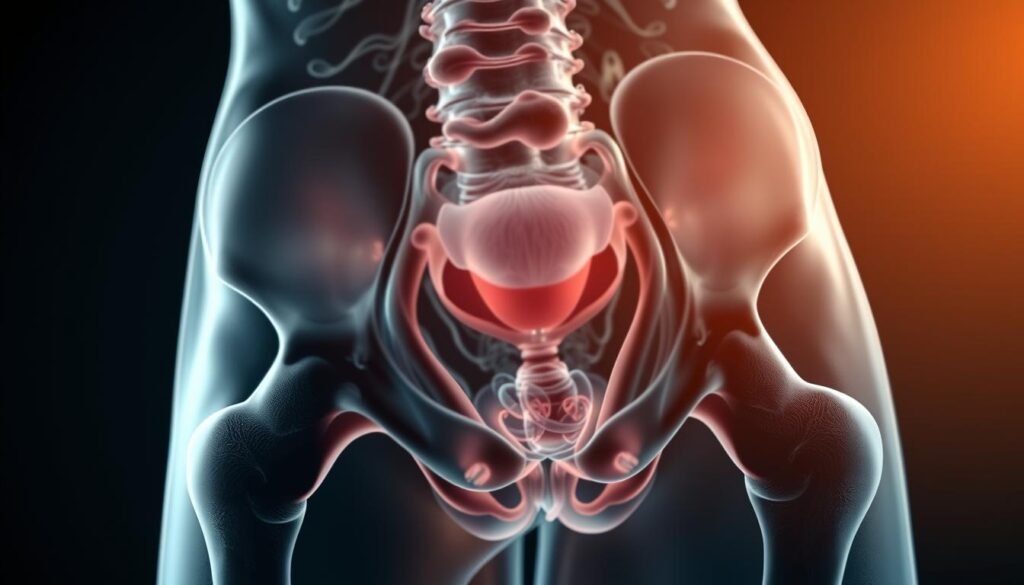

Grâce à des images en 3D, cette technologie permet aux médecins de repérer des lésions infimes avec une précision exceptionnelle. Elle est devenue incontournable pour explorer les pathologies complexes chez les femmes.

Détection précoce des tumeurs pelviennes

L’imagerie résonance identifie des tumeurs de moins de 1 cm, même dans les tissus profonds. Une étude marocaine révèle une précision de 92% pour le cancer de l’endomètre.

Évaluation précise de l’endométriose

Les séquences T2 et la suppression graisseuse cartographient les lésions d’endométriose en 3D. Cette méthode guide les chirurgiens pour des interventions plus ciblées.

Surveillance des fibromes utérins

Des algorithmes internationaux mesurent leur volume avec une marge d’erreur inférieure à 5%. Ideal pour suivre l’évolution sans examens invasifs.

Identification des anomalies gynécologiques

Elle dépiste les malformations comme l’utérus cloisonné ou bicorne. Les résultats orientent les décisions thérapeutiques en équipe pluridisciplinaire.